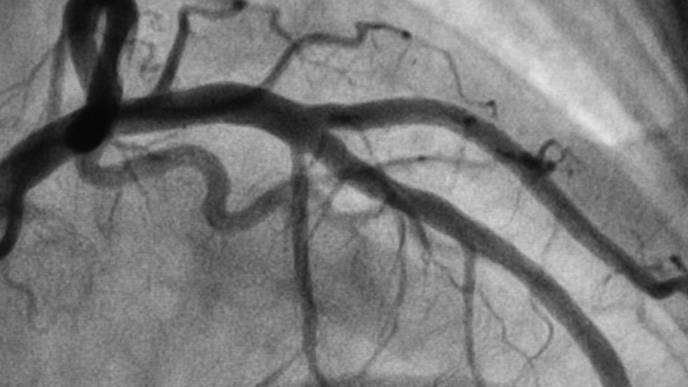

The trial focused on patients with angina, or chest pain due to plaque buildup in the coronary arteries, that is not adequately controlled with available treatments. The CSR is an hourglass-shaped stent designed to narrow the vein that collects blood from the heart muscle (the coronary sinus) and drive oxygen-rich blood back into areas of the heart muscle that may not be receiving enough blood.

All participants had symptomatic angina, ischemia and coronary artery disease with no further medical or interventional options at the start of the study. Participants underwent a cardiac MRI and treadmill exercise test before their procedure and at the end of a blinded six-month follow-up period. Patients also recorded their angina symptoms daily with a smartphone application.